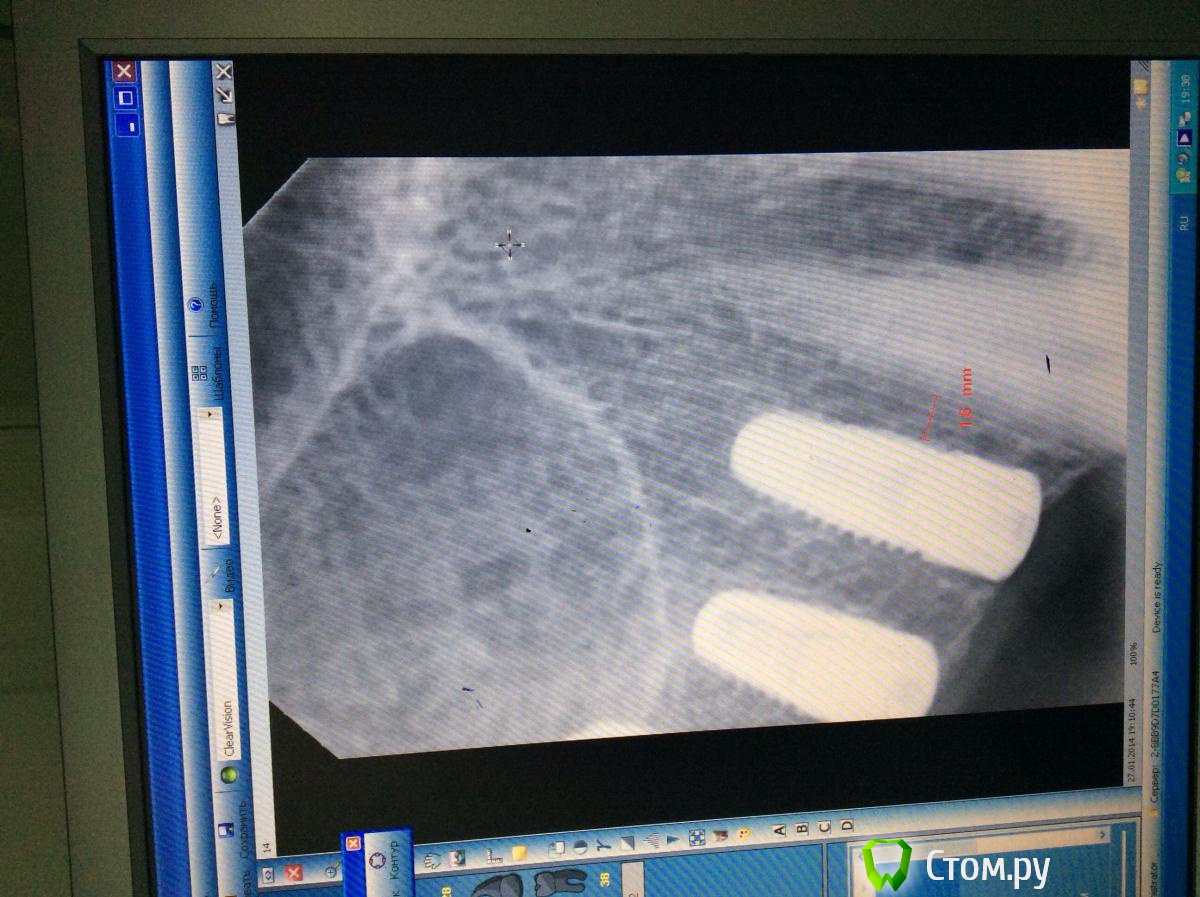

Opimar Опубликовано 30 октября, 2013 Автор Поделиться Опубликовано 30 октября, 2013 (изменено) Добрался до компьютера. Выкладываю сагитальные слева и справа и фронт. Соустье не видно. Изменено 30 октября, 2013 пользователем Opimar Ссылка на комментарий

Bier Опубликовано 31 октября, 2013 Поделиться Опубликовано 31 октября, 2013 там везде полно кости, зачем какой-то синус? Сомневаетесь, возьмите 8мм (и поставьте 3 имплантата), хотя туда спокойно 10мм войдет, КТ врет. 4 Ссылка на комментарий

Opimar Опубликовано 27 января, 2014 Автор Поделиться Опубликовано 27 января, 2014 (изменено) Последовав вашим рекомендациям выкладываю итог работы. ОРТО и прицельные снимки. Установил: 14-3.9 на 1015-3.9 на 816-4.4 на 8 16 бикортикальная фиксация, надеюсь проблем не будет. Стабилизация была, имплантанты не болтались закручиваю всегда вручную. Теперь будем посмотреть)) Система Biotech Изменено 27 января, 2014 пользователем Opimar Ссылка на комментарий